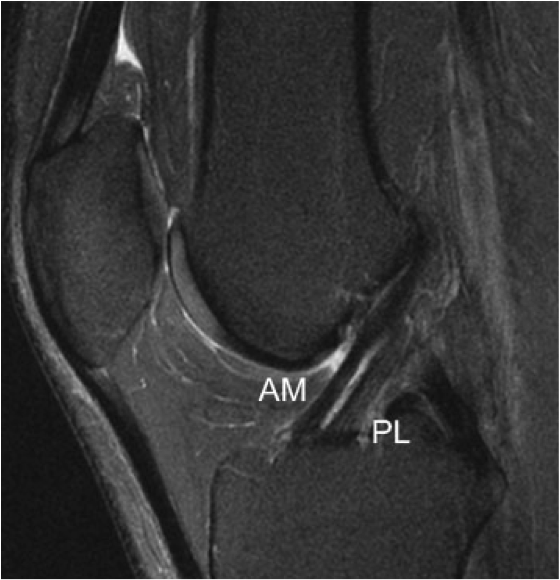

Le LCA est formé de plusieurs faisceaux de fibres dont les deux plus importants sont le faisceau antéro-médial AM et le faisceau postéro-latéral PL (par rapport à leur insertion tibiale).

Le faisceau AM (insertion tibial antérieure et médiale, insertion fémorale haute et postérieure) est défini de telle façon que ses fibres tibiales les plus antérieures deviennent les plus postérieures sur le fémur (longueur moyenne de 3,3 cm).

Le faisceau PL a une insertion tibiale en arrière et en dehors du faisceau antéro-médial; plus court et plus vertical il s'insère plus bas sur la face axiale du condyle externe.